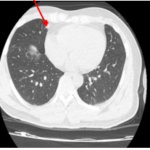

CASE LÂM SÀNG Điều trị bệnh nhân mắc đồng thời hai loại ung thư: Ung thư phổi và ung thư tuyến tiền liệt

CASE LÂM SÀNG Điều trị bệnh nhân mắc đồng thời hai loại ung thư: Ung thư phổi và ung thư...